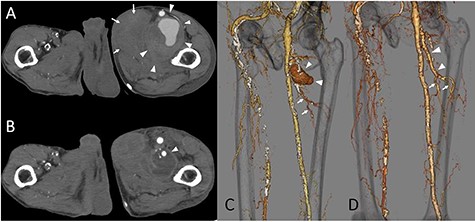

The patient looked pale but was conscious. He was thin and weighed 40 kg (body mass index, 14.5) due to loss of appetite after gastric surgery; however, his left thigh was reddish, edematous and painful (Fig. 1). Hemodynamics, such as blood pressure and heart rate, were stable. Blood tests revealed a hemoglobin level of 3.41 mmol/l. Ultrasonography showed a 72 × 52 mm PFAA with a thick thrombus and hematoma extending into the adductors (Fig. 2). A venous thrombus was also observed in the left femoral vein. Enhanced computed tomography (CT) revealed a ruptured left PFAA 64 × 54 mm in diameter (Fig. 3A and C). In addition, right iliac artery aneurysm and right CFA and SFA occlusion were also observed.

(A) The CT scan image. The deltas indicate the PFAA, which was 64 × 54 mm. The arrows indicate the hematoma inside the adductors. (B) Postoperative CT image. The delta point interposed the PFA. The hematoma inside the adductors decreased. (C) The 3-dimension image obtained by the CT scan. The deltas indicate the PFAA. The arrows indicate the terminal branches toward the muscles. (D) The 3-dimension image obtained by postoperative CT. The deltas point to the artificial graft. The arrows indicate the preserved branches from the PFA toward the muscles.

The patient’s postoperative recovery was uneventful. On postoperative Day 5, enhanced CT showed an interposed PFA with no complications, perforating branches originating from the distal portion of the interposed vessel and a reduction in the hematoma (Fig. 3B and D). The patient was discharged on postoperative Day 7.